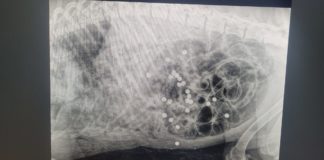

Labrador ucciso a fucilate, la rabbia della LNDC Animal Protection

Monta la rabbia per il caso dell'uccisione di un cane di razza Labrador, ucciso a colpi di fucile nella notte tra giovedì 13 e...